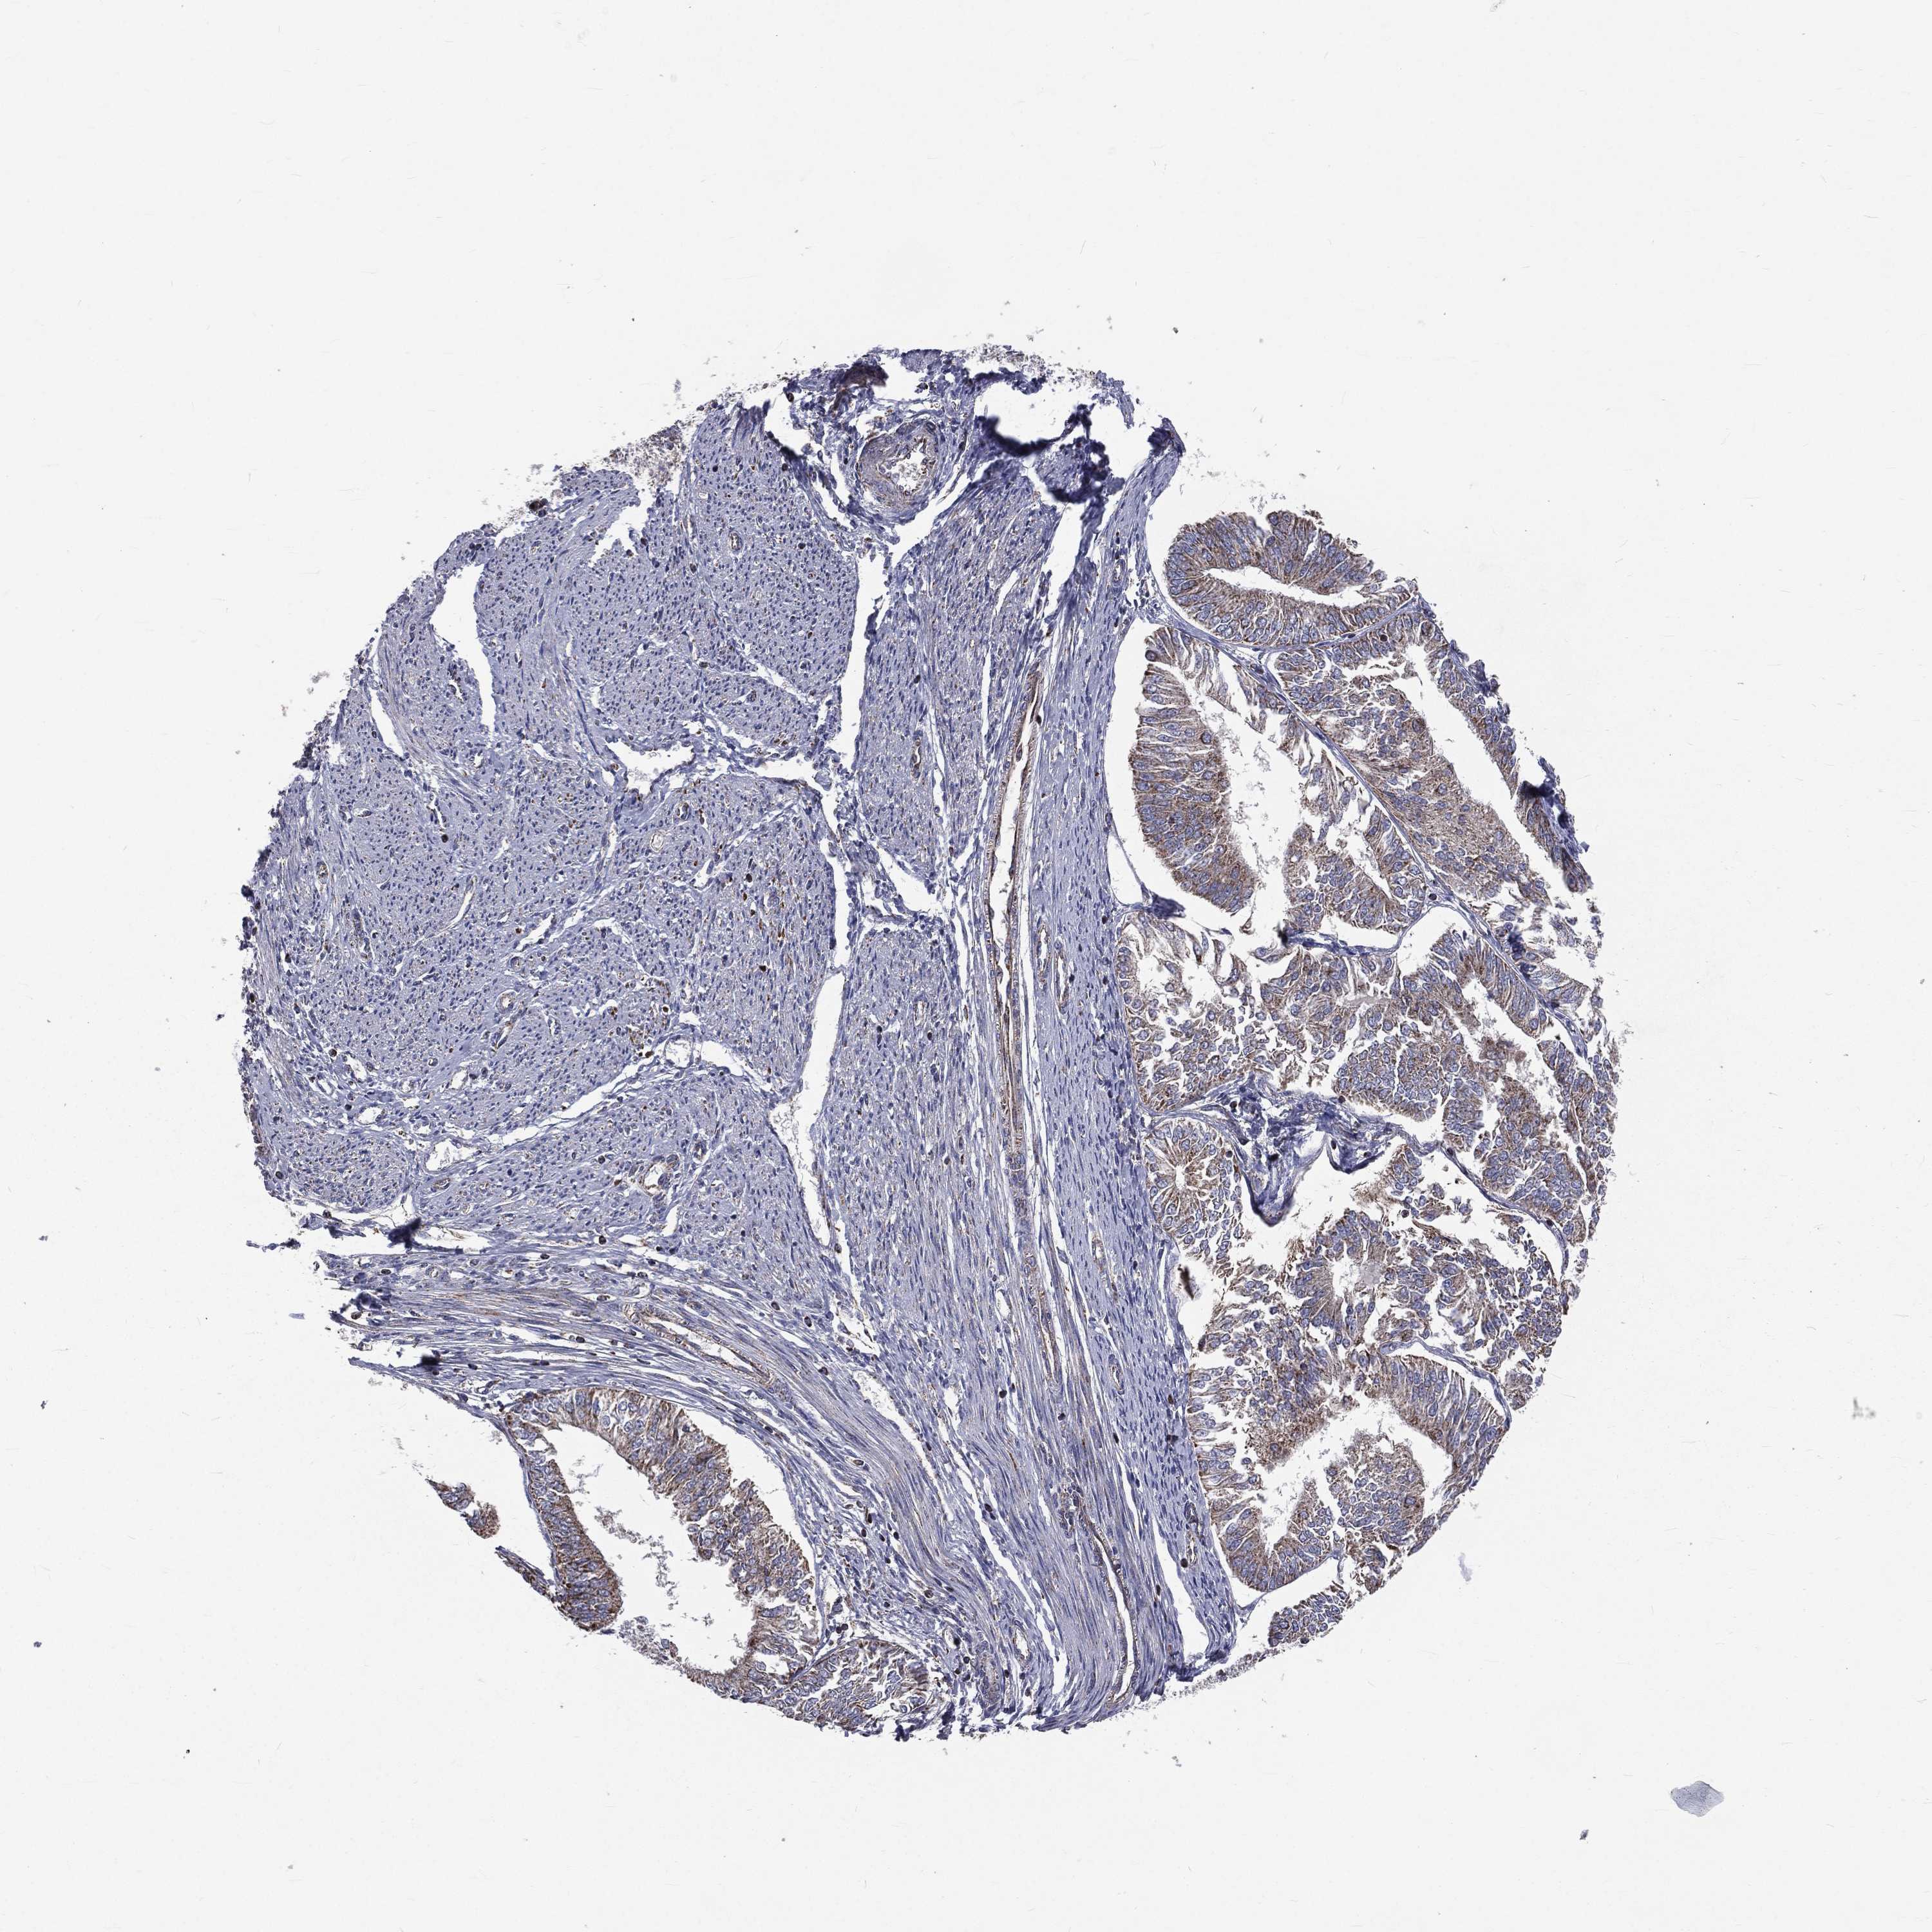

ENDOMETRIAL CANCER - Protein expressioni

A mouse-over function shows sample information and annotation data. Click on an image to view it in a full screen mode. Samples can be filtered based on level of antibody staining by selecting one or several of the following categories: high, medium, low and not detected. The assay and annotation is described here.

Note that samples used for immunohistochemistry by the Human Protein Atlas do not correspond to samples in the TCGA dataset.

Antibody stainingi

Antibody staining in the annotated cell types in the current human tissue is reported as not detected, low, medium, or high, based on conventional immunohistochemistry profiling in selected tissues. This score is based on the combination of the staining intensity and fraction of stained cells.

Each image is clickable and will lead to virtual microscopy that enables deeper exploration of all samples and also displays staining intensity scores, fraction scores and subcellular localization as well as patient and tissue information for each sample.

Antibody HPA044620

Antibody HPA058621

Staining

High

Medium

Low

Not detected

Intensity

Strong

Moderate

Weak

Negative

Quantity

>75%

75%-25%

<25%

None

Location

Nuclear

Cytoplasmic/membranous

Cytoplasmic/membranous,nuclear

Adenocarcinoma, NOS